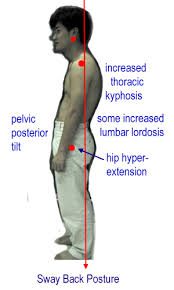

こんにちは!横浜本牧パーソナルトレーナー宮原崇です。 早いもので昨日は鏡開きでしたね。 さて、股関節にお悩みの方も多いと思いますが、今回は「Butt Griper」という症状をご紹介いたします。 主に股関節の前側や太もも…